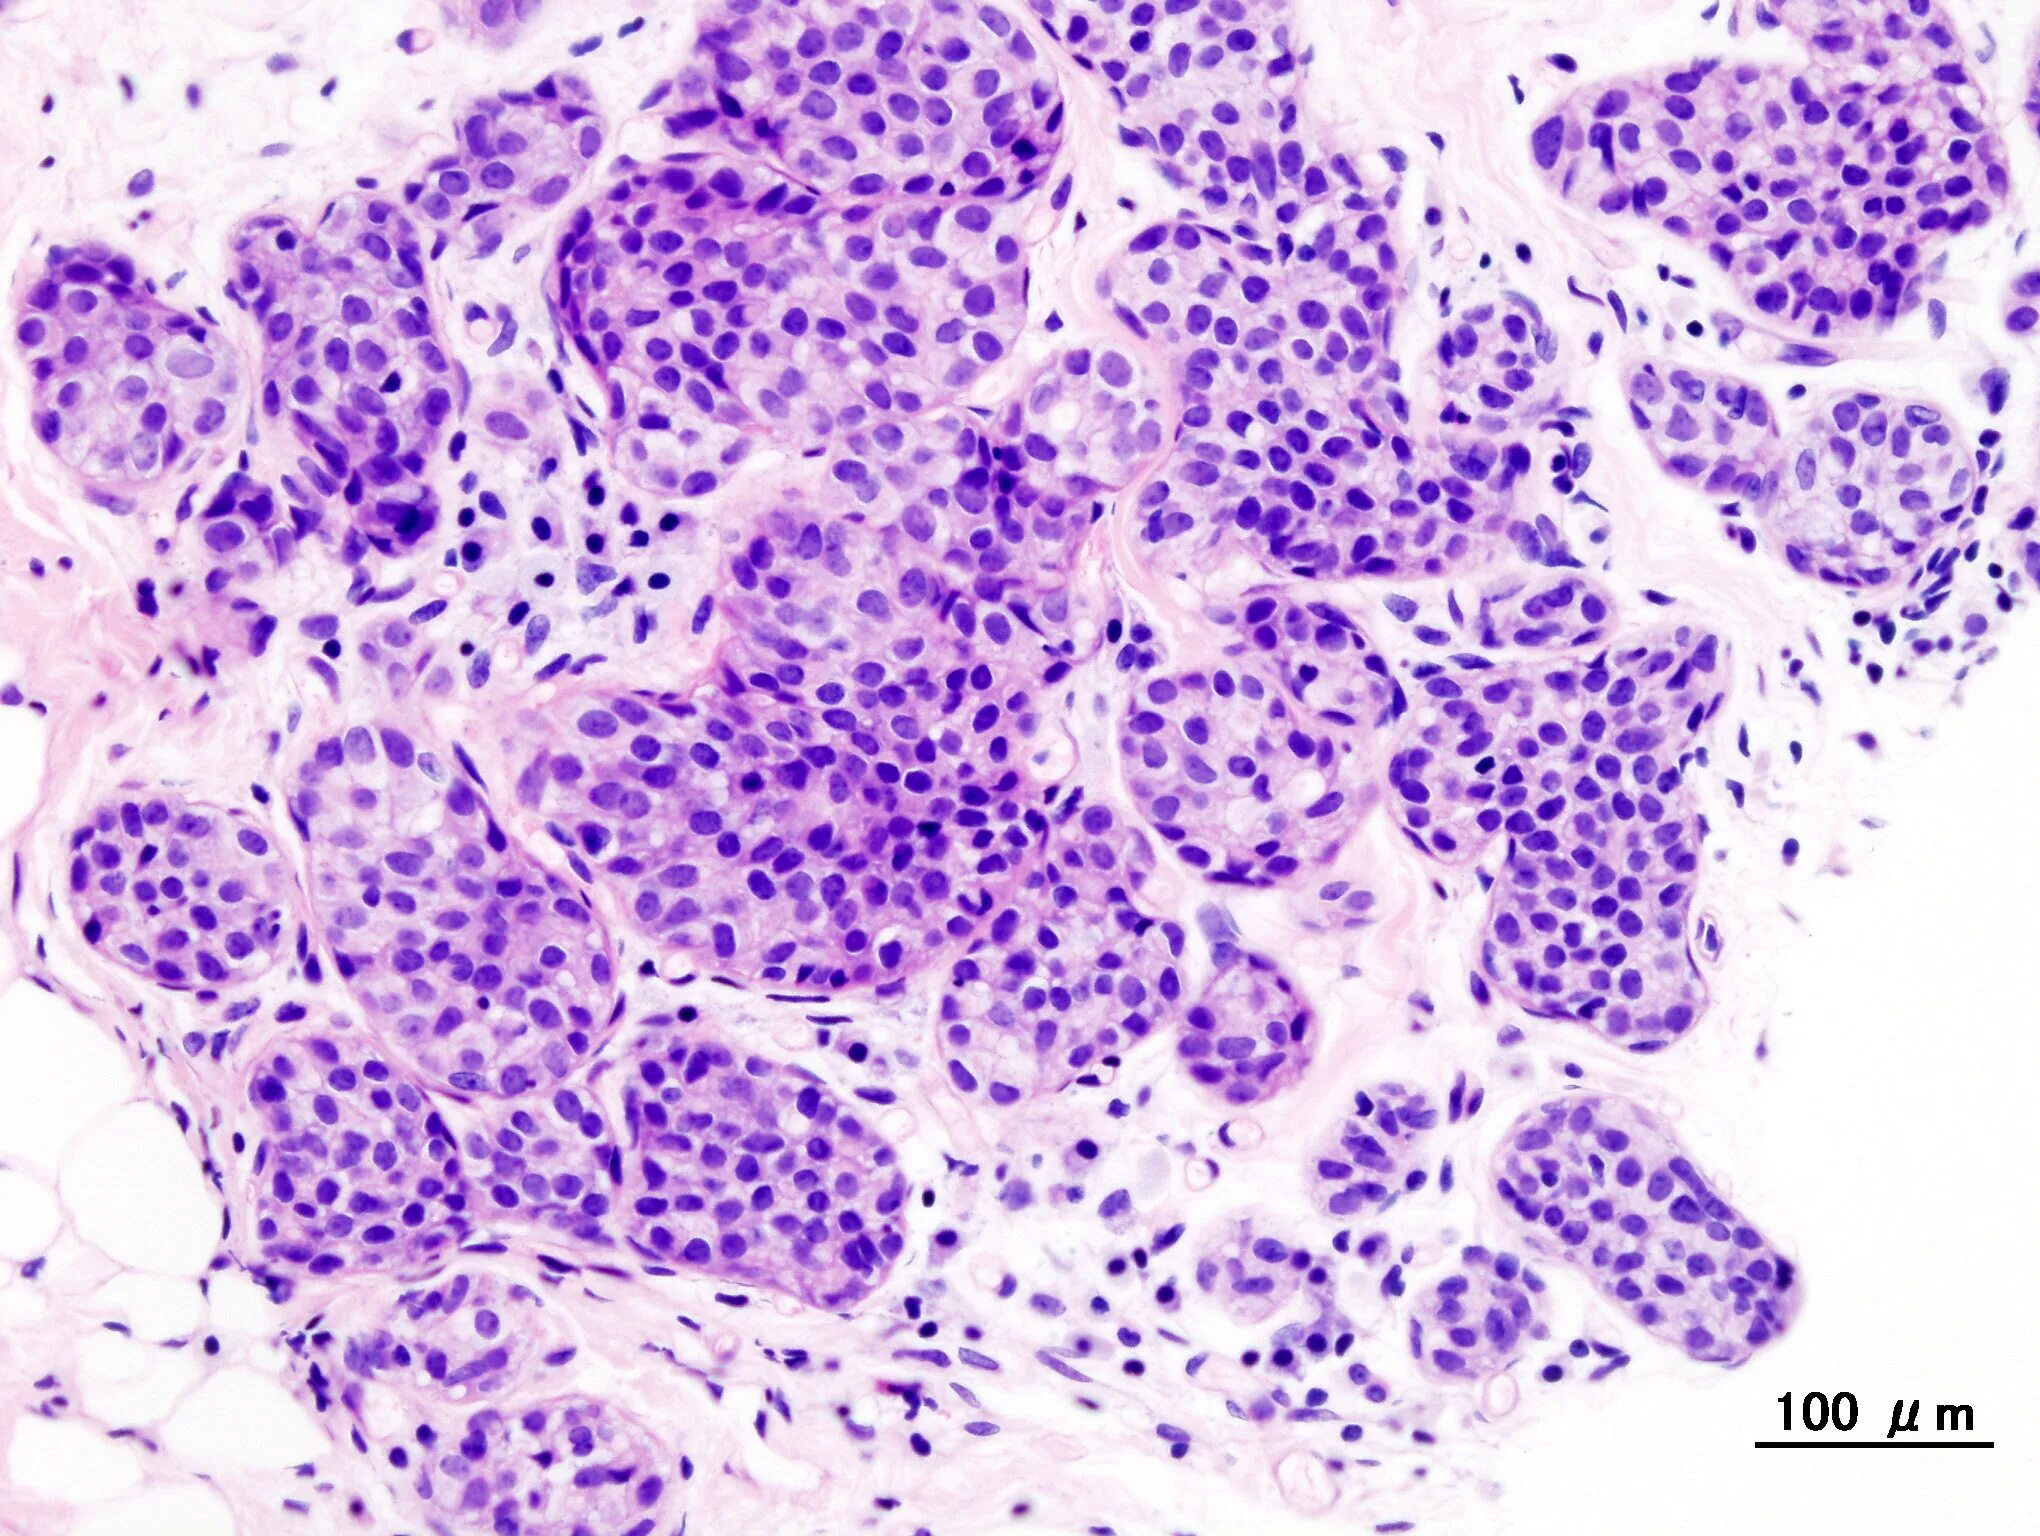

Атипичные клетки в гистологии